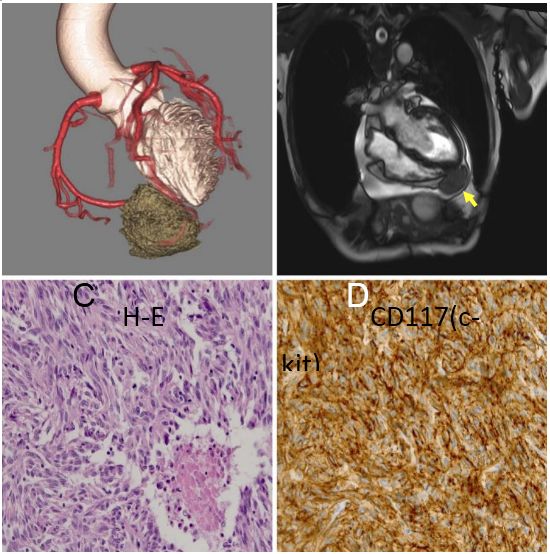

一例74岁患有原发性十二指肠间质瘤(GIST)的女性患者因心源性休克收入我院急诊科,死于心外肿瘤破裂导致的心脏骤停。冠状动脉CT血管造影(图A)显示肿瘤有来自右冠状动脉和左前降支的营养血管。心血管磁共振(图B)显示肿瘤(箭头)具有不均匀强化,起自心肌。患者选择接受保守治疗。尸检于心室浆膜下检测到一个7×8×7厘米的弹性软肿瘤。病理示呈纤维样增生的轻度非典型梭形细胞(图C),CD117(c-kit)阳性(图D)。因此,该心外肿瘤被诊断为GIST转移。虽然三分之二的GIST转移患者为肝转移,心脏转移较罕见。